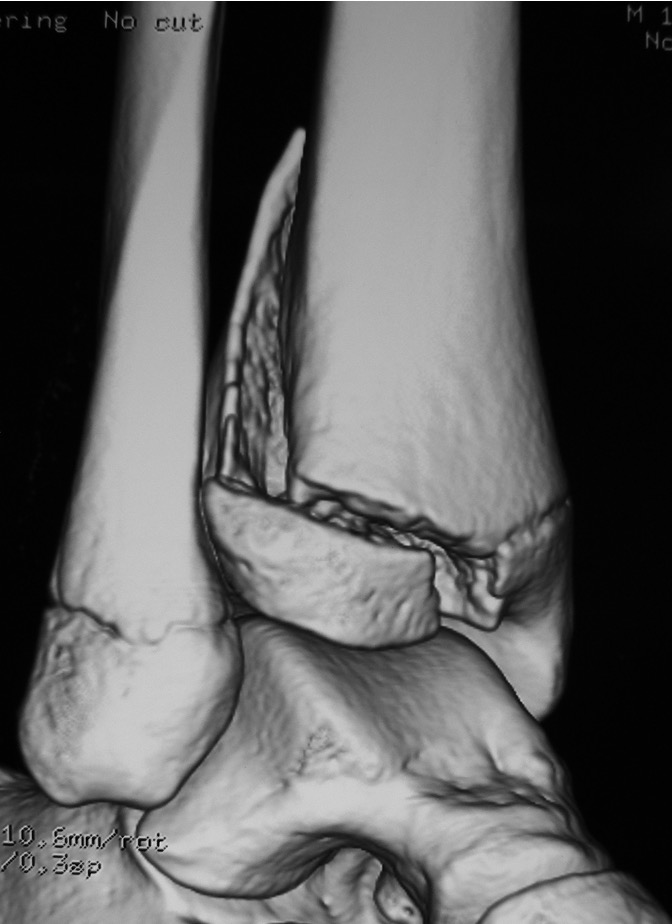

Triplanar Fracture

Definition

Fracture in coronal, sagittal and transverse planes

- crosses epiphysis

- passes through growth plate

- extends into metaphysis

Xray

AP xray: Salter-Harris type III / Tillaux

Lateral xray: Salter-Harris Type II

CT

Coronal images: Salter-Harris type III

Sagittal images: Salter-Harris type II

Axial images: 3 point star